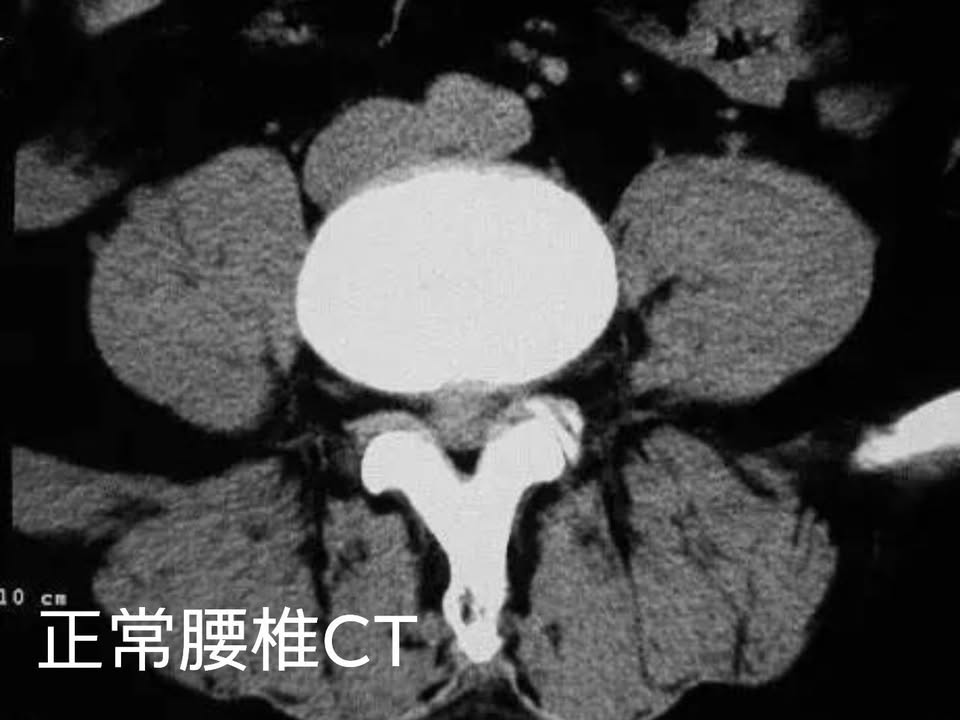

Cervical Spine Treatment Cases 腰椎治療案例 #腰椎手術失敗綜合症候群 #術後沒保養還是又繼續椎間盤突出 #感謝台北梁小姐熱情見證 ... 2021.03.02 #超感動醫案感謝中壢姚阿姨見證 #原本已經坐輪椅的人生看到一絲希望 #脊刻救援牛轉乾... 2021.02.22 #感謝新北中和區陳大哥熱情見證 #從北到南看過眾多中西醫民俗療法 #腰痛到連躺跟坐都... 2021.02.17 #感謝桃園龜山蘆先生熱情見證 #腰椎跟屁股痠痛超過十二年 #腰椎纖維環裂隙導致神經根... 2021.02.16 #騎馬摔傷腰椎醫案 #感謝內湖陳先生熱情見證 #椎間盤突出合併輕微椎間孔狹窄 #重新騎... 2021.02.03 #巨大椎間盤突出醫案 #脊椎整合中醫微創逆轉勝 #感謝三峽林先生熱情見證 #為何突出的... 2021.01.29 #腰椎粉碎性骨折手術後調養醫案 #坐輪椅的人生終於看到希望 #脊椎手術失敗症候群 #Fai... 2021.01.26 #感謝台中市大肚區患者熱情見證 #第二次治療腰痛好超多 #腰酸痛時間快一年了 #親筆寫... 2020.12.05 #腰椎嚴重滑脫醫案 #原本左腳麻痛無法久站超過十分鐘 #脊椎整合中醫微創療法逆轉勝 #... 2020.12.02 #感謝林口楊先生熱情見證 #椎間盤整和中西醫微創療法逆轉勝 #曾經大痛到無法走路嚴重... 2020.11.25 #今天來聊巨大骨刺為何可以吸收回去! #椎間盤突出需要多久才能吸收呢? #馬尾神經症候... 2020.11.10 #腰椎滑脫一定要開刀嗎? #骨科認為開刀置放骨釘穩定錐體 #如果患者可以藉由增強肌... 2020.11.04 #六年的長期腰酸痛醫案 #原來是椎管狹窄合併輕微突出 #每年冬天準時發作苦不堪言 #感... 2020.10.31 #椎管狹窄案例 #感謝新莊陳大哥熱情見證 #腰酸痛數年原來是椎管狹窄 #來診前已經痛到... 2020.10.28 #知名四代魚丸店掌門人熱情見證 #腰椎中醫微創逆轉勝 #椎間盤突出醫案 #感謝新北... 2020.10.23 ← 上一頁 8 9 10 11 12 下一頁 →